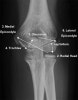

2. Elbow AP view

- Elbow Ossification Centres

A useful mnemonic for remembering the order of the ossification centres is the CRITOL rule

Capitellum

Radial head

Internal (medial epicondyle)

Trochlea

Olecranon

Lateral epicondyle

It is noteworthy that the ossification centres of the elbow do not always follow this order of ossification.